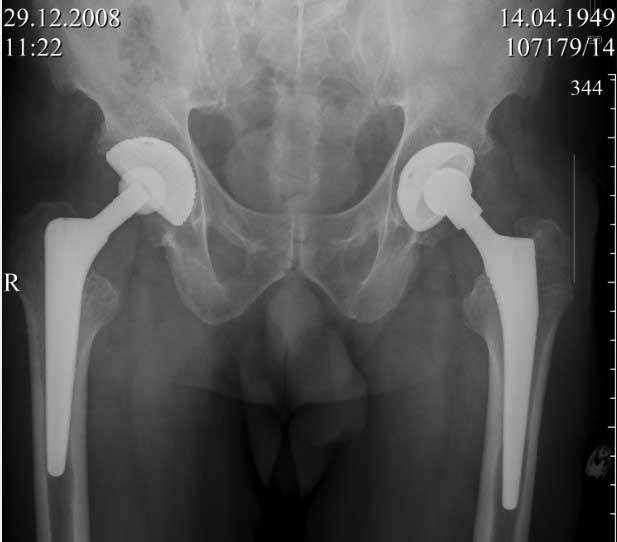

Пациент 60 лет, мужчина. Оперирован в 2007 году, поочередно оперированы два тазобедренных сустава с интервалом в 4 месяца. В 2008 году оперирован на сердце(аорто-коронарное шунтирование).Операция осложнилась инфицированием операционной раны в области грудины, лечился в гнойном отделении.

ниже снимок в 2008 году